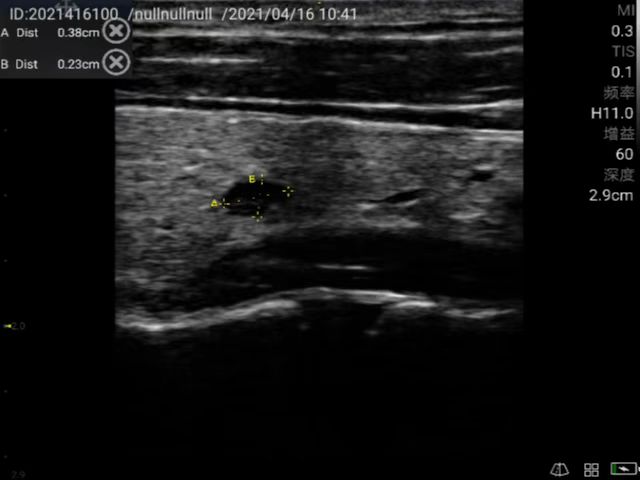

Accurate diagnosis of thyroid nodules and interventional guided puncture.

Breast and thyroid interventional ultrasound; Identify thyroid nodules and determine vascular lesions; Guide percutaneous biopsy to ensure accurate sampling; Guide fine needle aspiration to aspirate cysts.